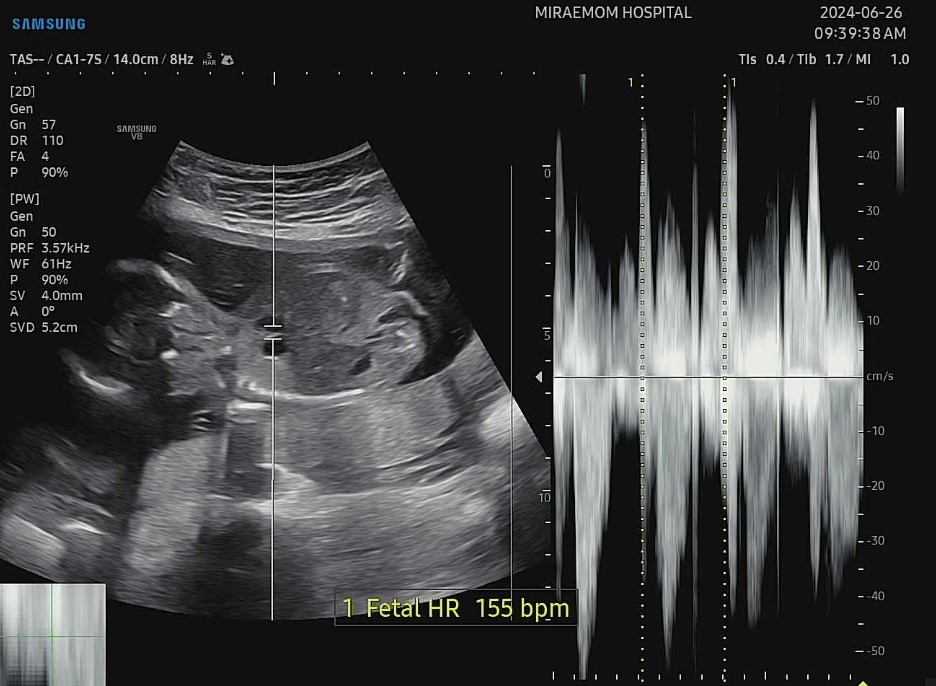

그래도 두 아이 모두 아주 잘뛰고 있는 심장소리에 마음은 놓였답니다^^*

엄마는 죽을것같은데 너무 잘 있는 우리 아들둥이들~ 볼때마다 사랑스러워요ㅎㅎ